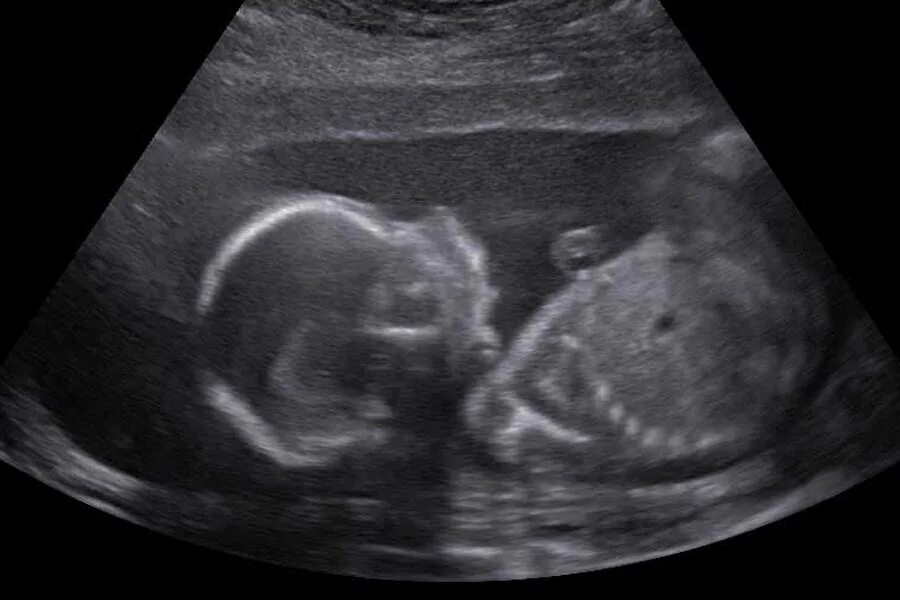

Как выглядит ребенок в 22 недели